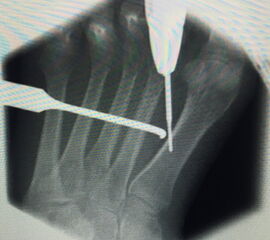

Werden komplette Osteotomien an den Zehen durchgeführt, fädeln wir die Osteotomien mit einem 1.2 oder 1.4 mm Kirschner-Draht auf, damit die einzelnen Fragmente nicht verkippen (Abb. 22).

Abb. 22 a-d: Präoperative Klauenzehen beim Jugendlichen in zwei Ansichten (a-b) und postoperative Auffädelung mit Kirschner-Drähten linker und rechter Fuß (c-d).

Zum Lesen der Bildbeschreibung und zur Vollansicht bitte die Bilder anklicken. Bilder: A. Helmers.

Nach unserer Erfahrung können komplette Osteotomien nicht so gut in einem Tapeverband stabil gehalten werden. Im Fall von Derotationen kombinieren wir einen Draht mit externen Tapezügeln, um das Ergebnis zu sichern. Die Drähte werden 2-3 Wochen belassen und anschließend in der Sprechstunde gezogen. Anschließend wird die Zehe noch 2 weitere Wochen mit Tape gezügelt (Abb. 23).